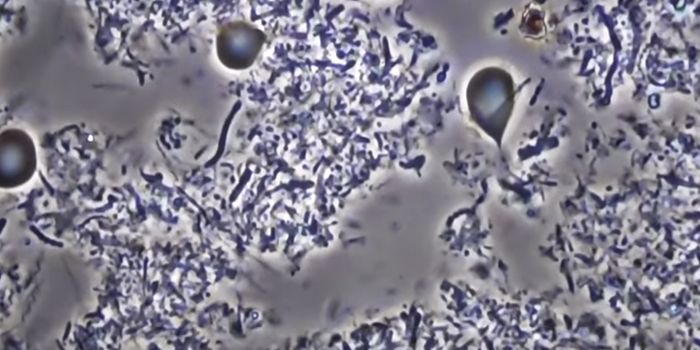

NOV 02, 2021MicrobiologySyphilis is on the rise worldwide, and it's killing infants. The disease is a leading cause of stillbirth worldwide, acc ...